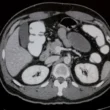

الأشعة المقطعية، المعروفة اختصارًا بـ CT أو CAT Scan، هي تقنية تصوير طبية تستخدم جهاز كمبيوتر خاص ومجموعة من الأشعة السينية لإنشاء صور مفصلة مقطعية (شرائح) لأعضائك الداخلية، العظام، الأنسجة الرخوة، والأوعية الدموية. تُعد هذه التقنية ذات قيمة لا تقدر بثمن في تشخيص مجموعة واسعة من الحالات الطبية.

يستخدم الأطباء الأشعة المقطعية للكشف عن الكسور، تحديد مكان الأورام، تقييم الإصابات الداخلية بعد الحوادث، تشخيص أمراض القلب، اكتشاف الجلطات الدموية، وتوجيه الإجراءات الطبية مثل الخزعات. بفضل قدرتها على توفير رؤية شاملة وتفصيلية، تُسهم الأشعة المقطعية بشكل كبير في دقة التشخيص وسرعة العلاج.

• صور تفصيلية: توفر الأشعة المقطعية صورًا عالية الدقة للعظام، الأنسجة الرخوة، والأوعية الدموية، مما يفوق تفاصيل الأشعة السينية التقليدية بكثير.